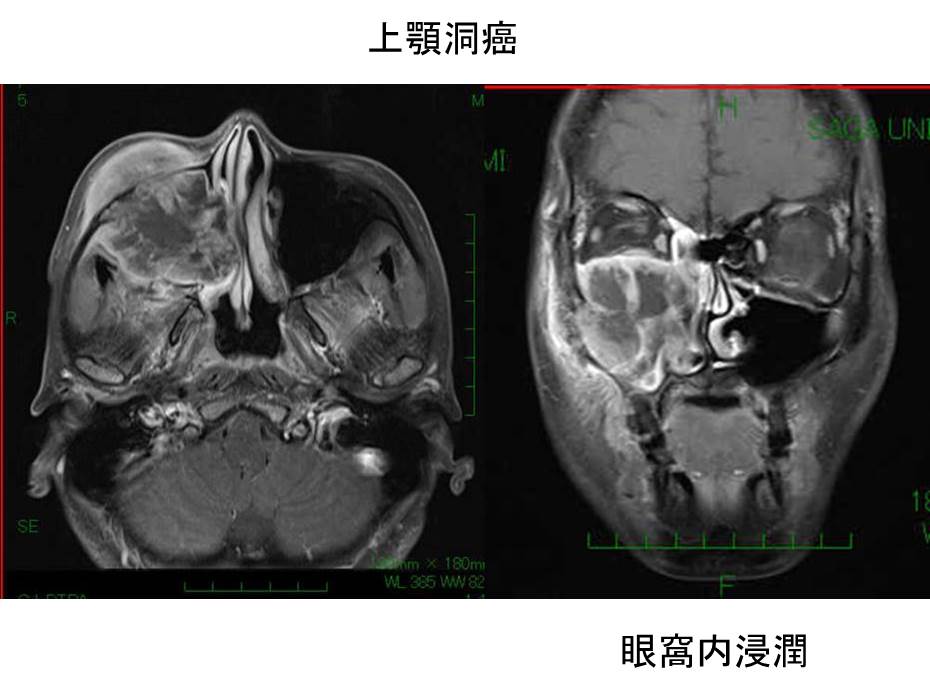

中咽頭癌 ct. 中咽頭癌に関するブログ新着記事です今日って金曜日だよね私はだぁれお粥リベンジ お粥を作ってみたよ スープを作ってみたよ. Ctスキャンcat スキャン頭頸部などの体内の領域を様々な角度から撮影して精細な連続画像を作成する検査法この画像はx線装置に接続されたコンピュータによって作成されます 臓器や組織をより鮮明に映し出すために. 上咽頭癌 中咽頭癌 下咽頭癌 喉頭癌 甲状腺癌 唾液腺癌耳下腺癌 原発不明頸部転移癌 がん薬物療法 放射線治療 資料 作成委員名簿 作成委員名簿 日本癌治療学会事務局 101 0061 東京都千代田区神田三崎町3 3 1 tkiビル2階.

小唾液腺 口腔 中咽頭疾患のct Mri 画像診断 33巻3号 医書 Jp

2 中咽頭のct Mri 耳鼻咽喉科 頭頸部外科 67巻11号 医書 Jp